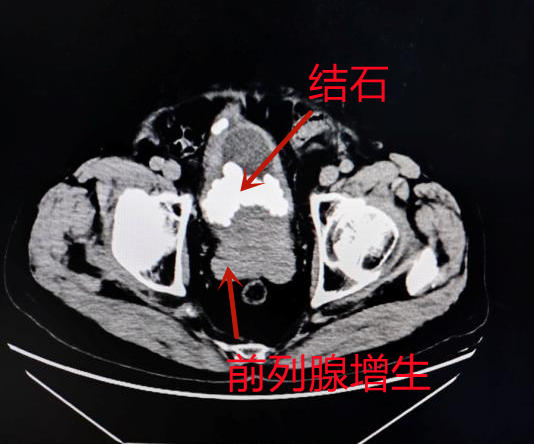

图片

泌尿外科主任唐汇龙介绍,一般情况下,前列腺增生合并膀胱结石的患者可以采取经尿道膀胱结石激光碎石取石术+经尿道前列腺激光剜除术的手术方式,一次解决两个问题。

然而,李嗲嗲的膀胱结石体量巨大,通过经尿道激光碎石的方式,难以在短时间内完成手术,将增大手术风险。

针对李嗲嗲的病情,泌尿外科组织开展科内会诊讨论,唐汇龙主任和杨华伟副主任医师决定,采取耻骨上膀胱造瘘取石术+经尿道前列腺激光解剖性剜除术,在患者的膀胱上打一个小洞,将结石一次性清理出来,同期经尿道进行前列腺剜除,最大程度缩短手术时间,减少手术伤害。